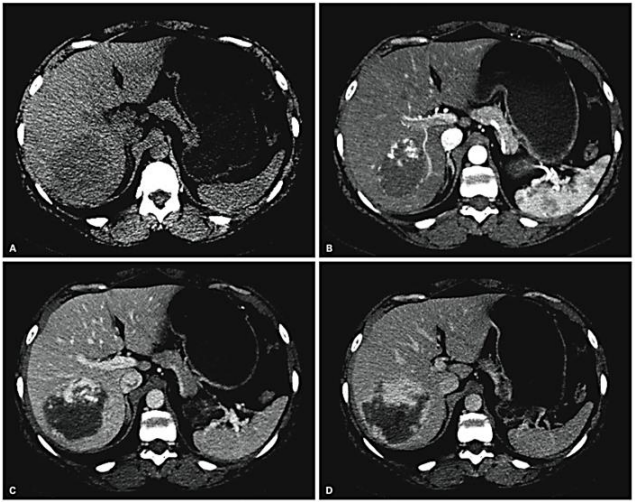

Assinale a alternativa que apresenta qual o provável diagnóstico da lesão hepática abaixo representada.

Provas